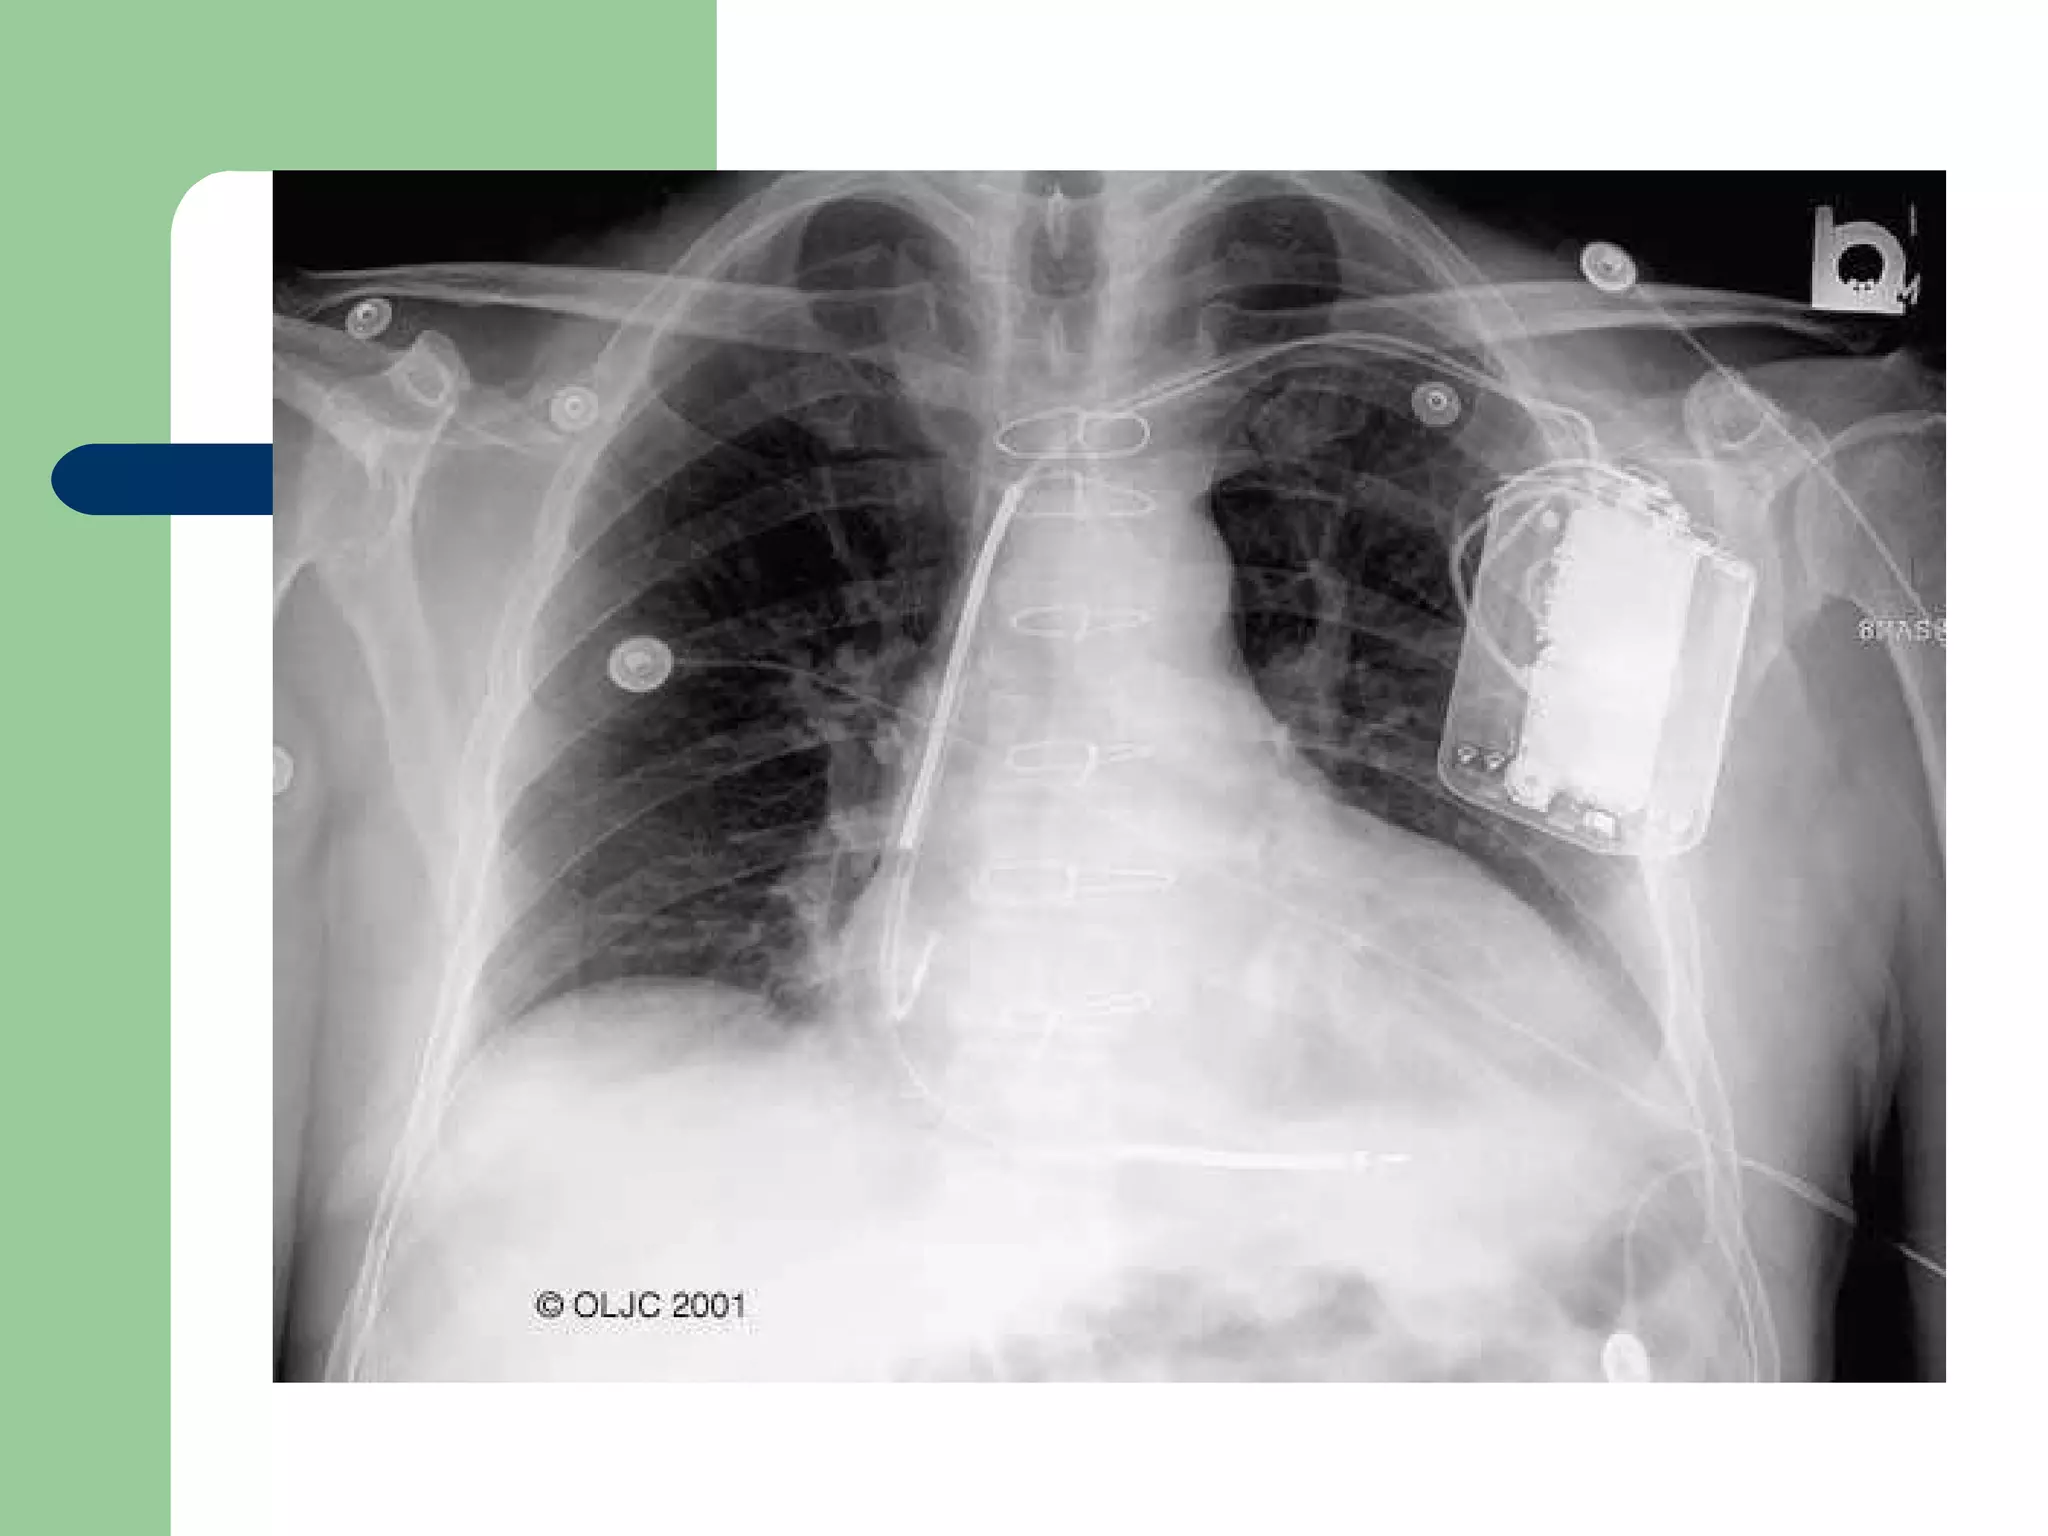

Pacemaker today!

Pacemaker today-Small devices pectoral site. First-line therapy for VT/VF patients Treatment of atrial arrhythmias Cardiac resynchronization therapy for HF Transvenous, single incision Local anesthesia; conscious sedation Short hospital stays and few complications Perioperative mortality < 1% Programmable therapy options Single- or dual-chamber therapy Battery longevity up to 9 years More than 100,000 implants/year